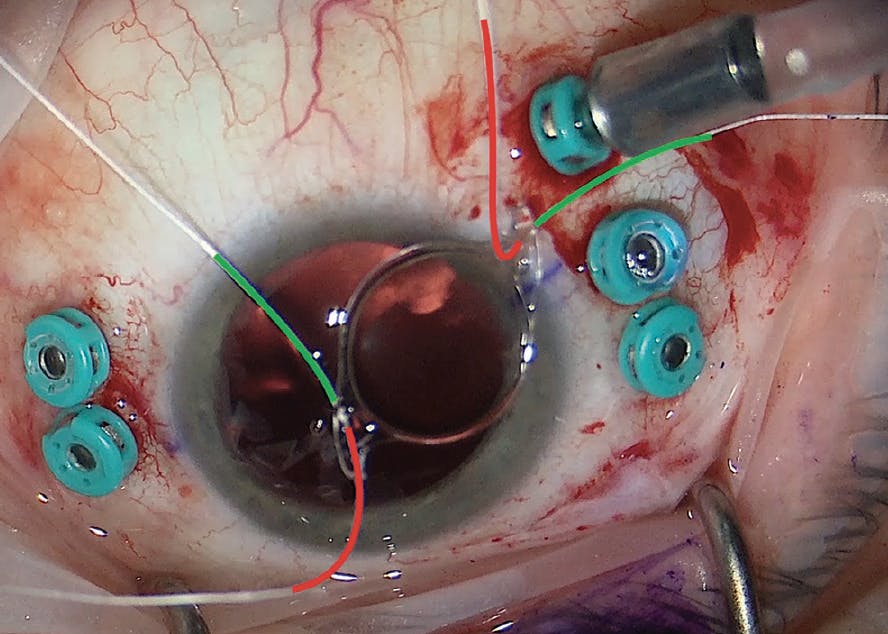

We inject a miotic agent before placing the ACIOL to create a scaffold for the viscoelastic and the IOL and make it easier to perform a peripheral iridotomy (PI). A glide-sheet can help guide the ACIOL but can also gape the wound and lead to iatrogenic injury. We prefer to use Kelman-McPherson forceps to grasp and deliver the ACIOL into the distal angle and then use a second instrument to push the externalized haptic into the subincision angle (Figure 1). We find that temporarily clamping any posterior infusion during ACIOL insertion can help mitigate iris prolapse. Once the ACIOL is placed, it can be rotated using a second instrument. We recommend lifting each haptic centrally and anteriorly to ensure there is no iris tuck or capture.

<p>Figure 1. When inserting an ACIOL, we first grasp the IOL lengthwise across the optic using Kelman-McPherson forceps (A). We then insert the ACIOL into the eye and place the leading haptic directly into the distal angle (B). We use a second instrument to push the trailing haptic (C), which compresses the ACIOL and allows it to be fully inserted into the eye (D).</p>

Figure 1. When inserting an ACIOL, we first grasp the IOL lengthwise across the optic using Kelman-McPherson forceps (A). We then insert the ACIOL into the eye and place the leading haptic directly into the distal angle (B). We use a second instrument to push the trailing haptic (C), which compresses the ACIOL and allows it to be fully inserted into the eye (D).

<p>Figure 4. During this Gore-Tex suture fixation of an MX60E IOL, the haptics are trimmed, and the Gore-Tex suture is passed through each eyelet in opposite orientation to allow a pseudo-four-point fixation. The red lines denote the sutures anterior to the IOL, and the green lines denote sutures posterior to the IOL.</p>

Figure 4. During this Gore-Tex suture fixation of an MX60E IOL, the haptics are trimmed, and the Gore-Tex suture is passed through each eyelet in opposite orientation to allow a pseudo-four-point fixation. The red lines denote the sutures anterior to the IOL, and the green lines denote sutures posterior to the IOL.